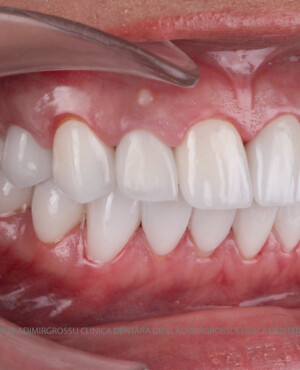

Transformările estetice și impactul reabilitării asupra vieții pacienților

Reabilitarea dentară produce o schimbare vizibilă și profundă în aspectul pacientului, cu efecte pozitive evidente asupra stimei de sine și a calității vieții. Mulți pacienți relatează bucuria redobândirii funcției masticatorii și dispariția complexelor legate de aspectul dentar.